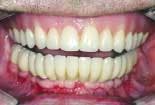

When the final restorations are received from the lab, they are inspected on the mounted models (figures 26 and 27). The final restoration is placed in the mouth and screwed in place. The access holes are filled with Clip, pink opaque composite and tooth-colored composite (figures 28 and 29). Final occlusal adjustments are made and esthetics confirmed (figure 30).